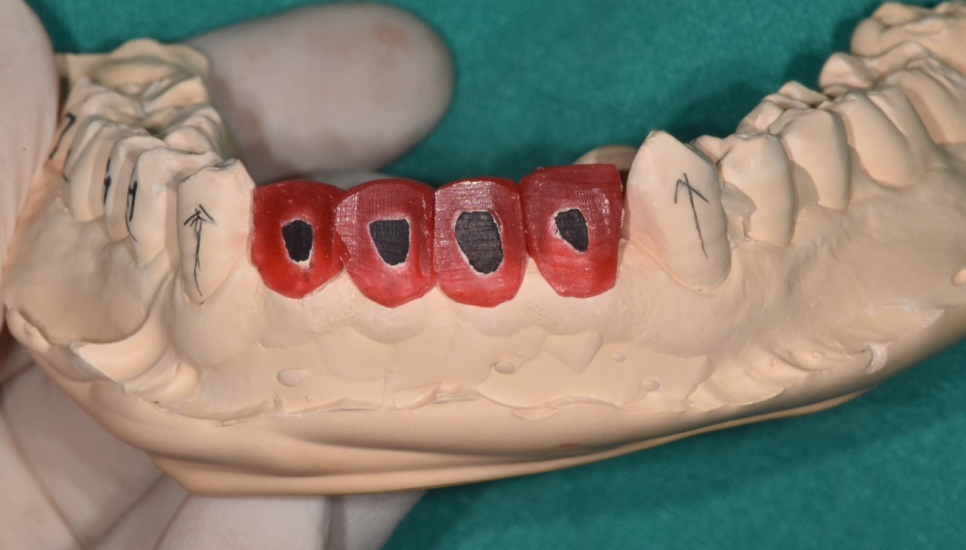

기공소와 협의를 통해 치아 예상 크기와 모양을 예측하고

제작해나갔는데요

위아래 4개씩 치아를 삭제하여 공간을 재분배

앞니 사이 간격 넓어짐 어떻게 공간을 메꿨는지

함께 보실까요~??